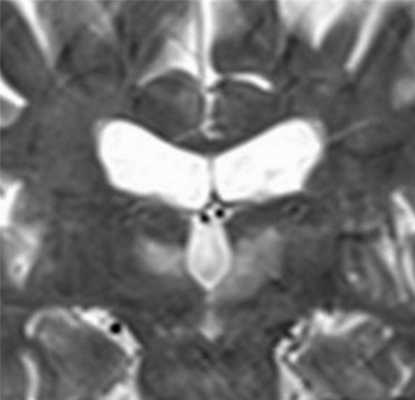

МРТ головного мозга. Т2-взвешенная корональная МРТ. Высокий сигнал от зрительных бугров при энцефалопатии Вернике.

При энцефалопатии Вернике на Т2-взвешенных МРТ головного мозга симметрично поражаются зрительные бугры, пластина четверохолмия и сосочковые тельца, иногда с участками кровоизлияний.

МРТ головного мозга позволяет найти типичные признаки энцефалита Вернике - атрофия сосочковых тел, их контрастное усиление на Т1-взвешенных МРТ с контрастированием и общую атрофию мозга. При МРТ головного мозга также описаны высокий сигнал на Т2-взвешенных изображениях от от зрительных бугров, вокруг водопровода